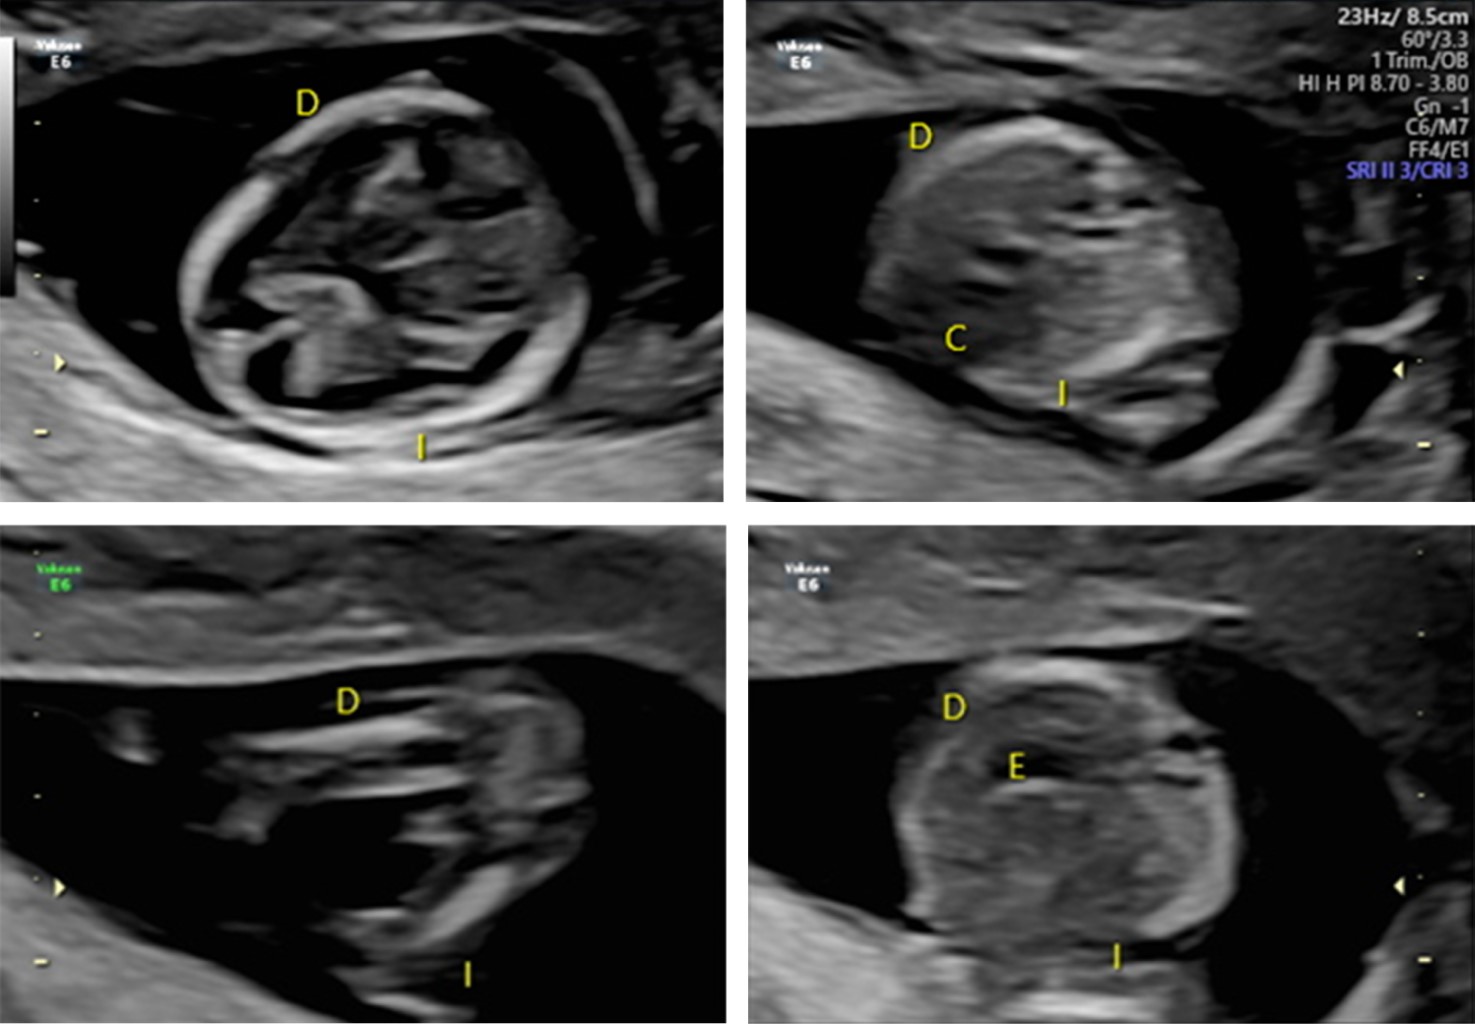

Tiene una frecuencia de 1 en cada 10,000 recién nacidos vivos y tiene gran relevancia dado que se asocia con malformaciones cardiacas y abdominales, las cuales se deben diagnosticar de manera prenatal a través del ultrasonido de tamizaje del primer trimestre del embarazo (Figura 3). Se debe emplear el Doppler color para la confirmación de cardiopatías. En este síndrome se agrupan variantes y diferentes grados de afectación (Figura 4).

Mujer de 26 años, gesta tres, un aborto, una cesárea, con embarazo de 35.1 semanas y ruptura prematura de membranas, con antecedente de feto con trisomía 18 (síndrome de Edwards) en gestación anterior. A la exploración física se registran frecuencias cardiacas fetales de 90 lpm. Después del nacimiento se confirma comunicación intraventricular y se estima que el recién nacido sea intervenido quirúrgicamente al año de vida.

Figura 4